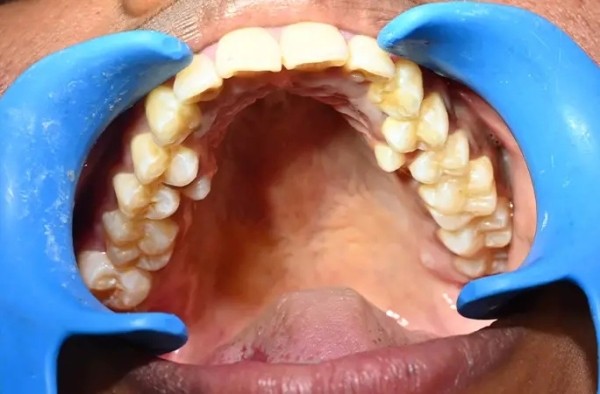

У девушки на шесть зубов больше, чем у большинства людей: у жительницы Индии насчитали 38 зубов вместо 32-ух. При этом у неё нашли ещё два зуба, которые не прорезались. Больше только у мужчины из Канады — 41 штука.

По словам Калпаны, эти лишние зубы у нее с юности. Родители девушки рекомендовали ей удалить лишние зубы, однако она побоялась. Кроме того, дополнительные зубы не доставляли Калпане никакого неудобства, и она решила их сохранить.